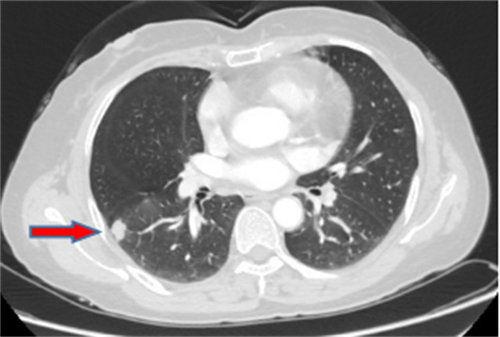

王女士,57岁,体检发现右下肺结节2月,术后病理诊断肺结节为肺隐球菌病。

李先生,45岁,发现右上肺结节2年,近期长大,术后病理诊断肺结节为炎性假瘤。

龙先生,65岁,体检发现右下肺结节,术后病理诊断肺结节为硬化性血管瘤。

郭女士,63岁,体检发现右下肺结节20天,术后病理诊断肺结节为浸润性腺癌。

王女士,65岁,体检发现右上肺磨玻璃结节16天,术后病理诊断肺结节为浸润性腺癌。

王女士,52岁,体检发现右上肺磨玻璃结节7月,术后病理诊断肺结节为原位腺癌。

王女士,35岁,新冠核酸检查阳性7天,胸部CT检查左上肺磨玻璃影,考虑新冠病毒性肺炎。